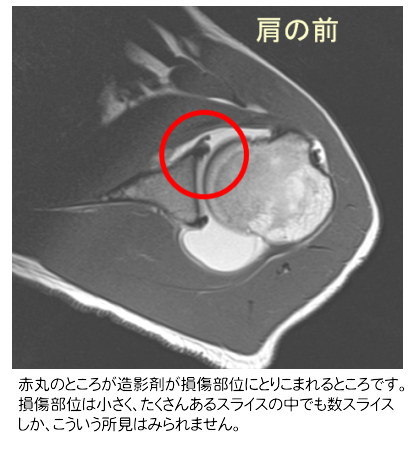

画像は造影MRIという検査を行い、診断をつけます。肩関節の中に造影剤のはいった生理食塩水を注入し、MRI撮影をおこないます。下の図)の青丸は造影剤の取り込み、損傷部位には造影剤がこぼれおちます。関節唇は関節窩というところにぴっちりついています。もし、はがれているとそこに水が流れ落ちます。MRIでわかりやすくするために造影剤をまぜておきます。

造影MRI